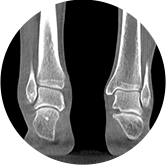

• 足踝

独特的负重位三维影像

填补常规CT/MR空白

助力术前规划和术后评估